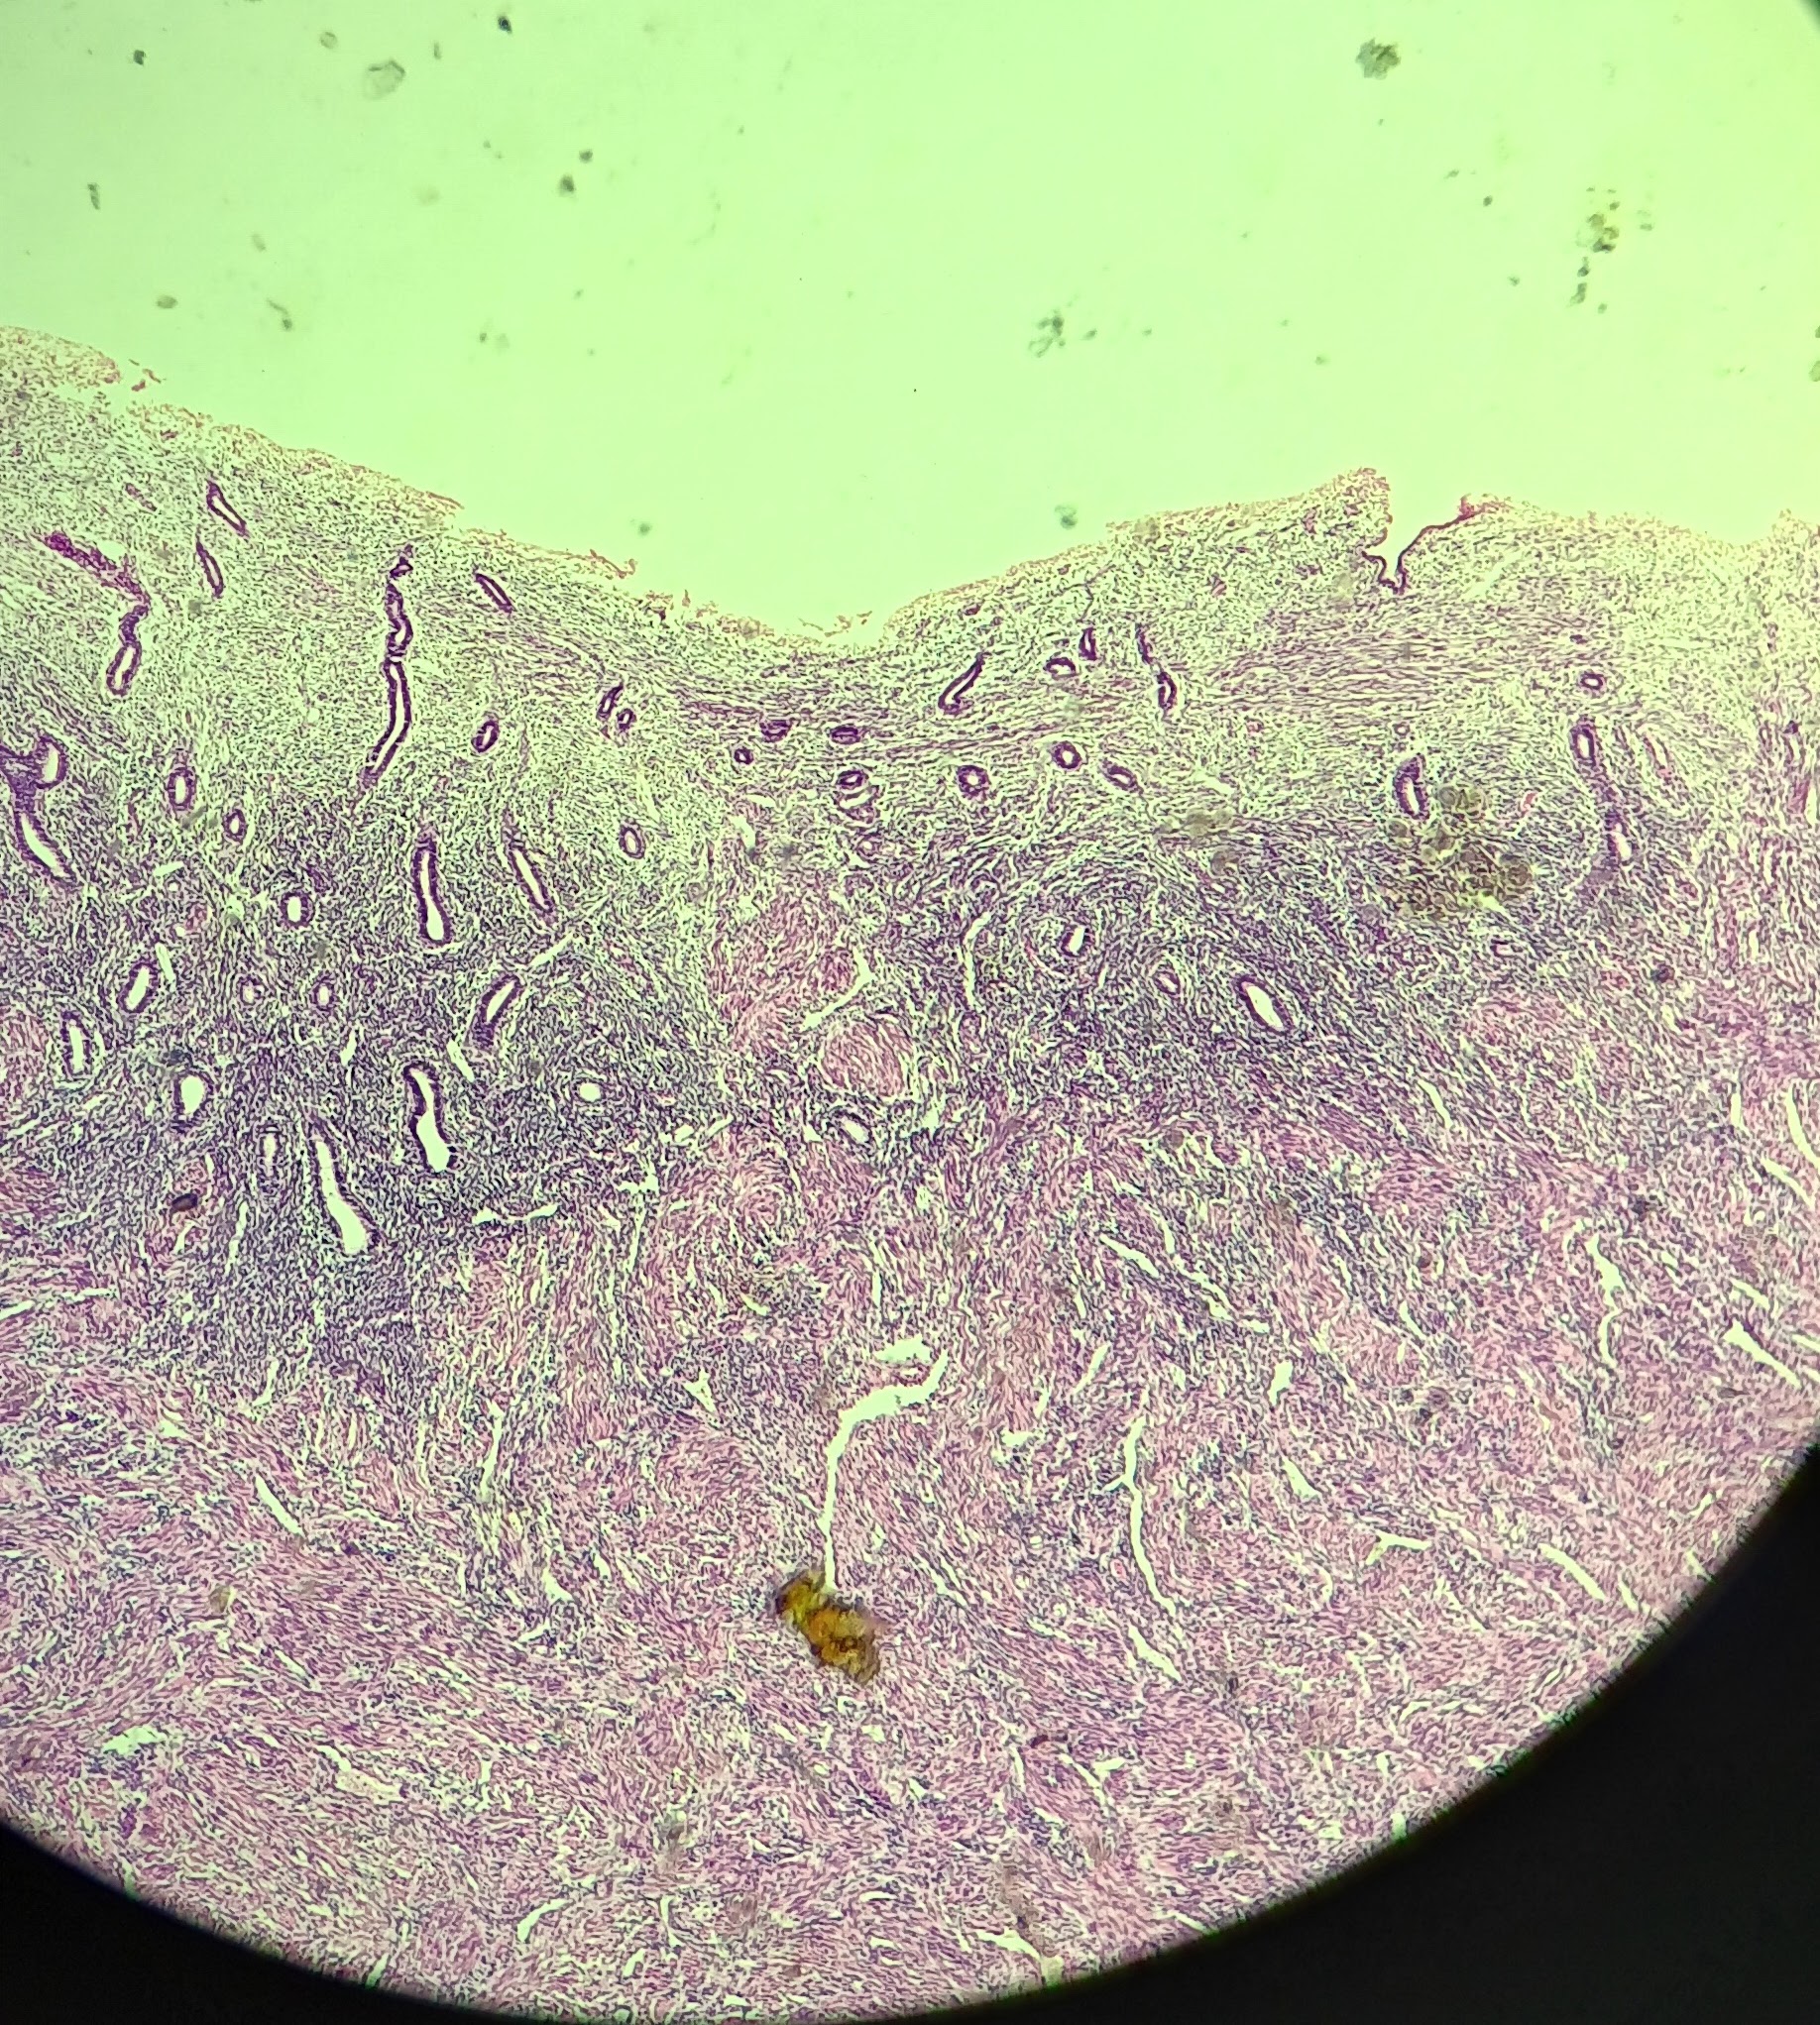

Perimetrium

Perimetrium

Myometrium

Myometrium

Endometrium

Endometrium

proliferate functional layer

secretory functional layer

menstrual functional layer

proliferate basal layer

secretory basal layer

menstrual basal layer

Uterine gland